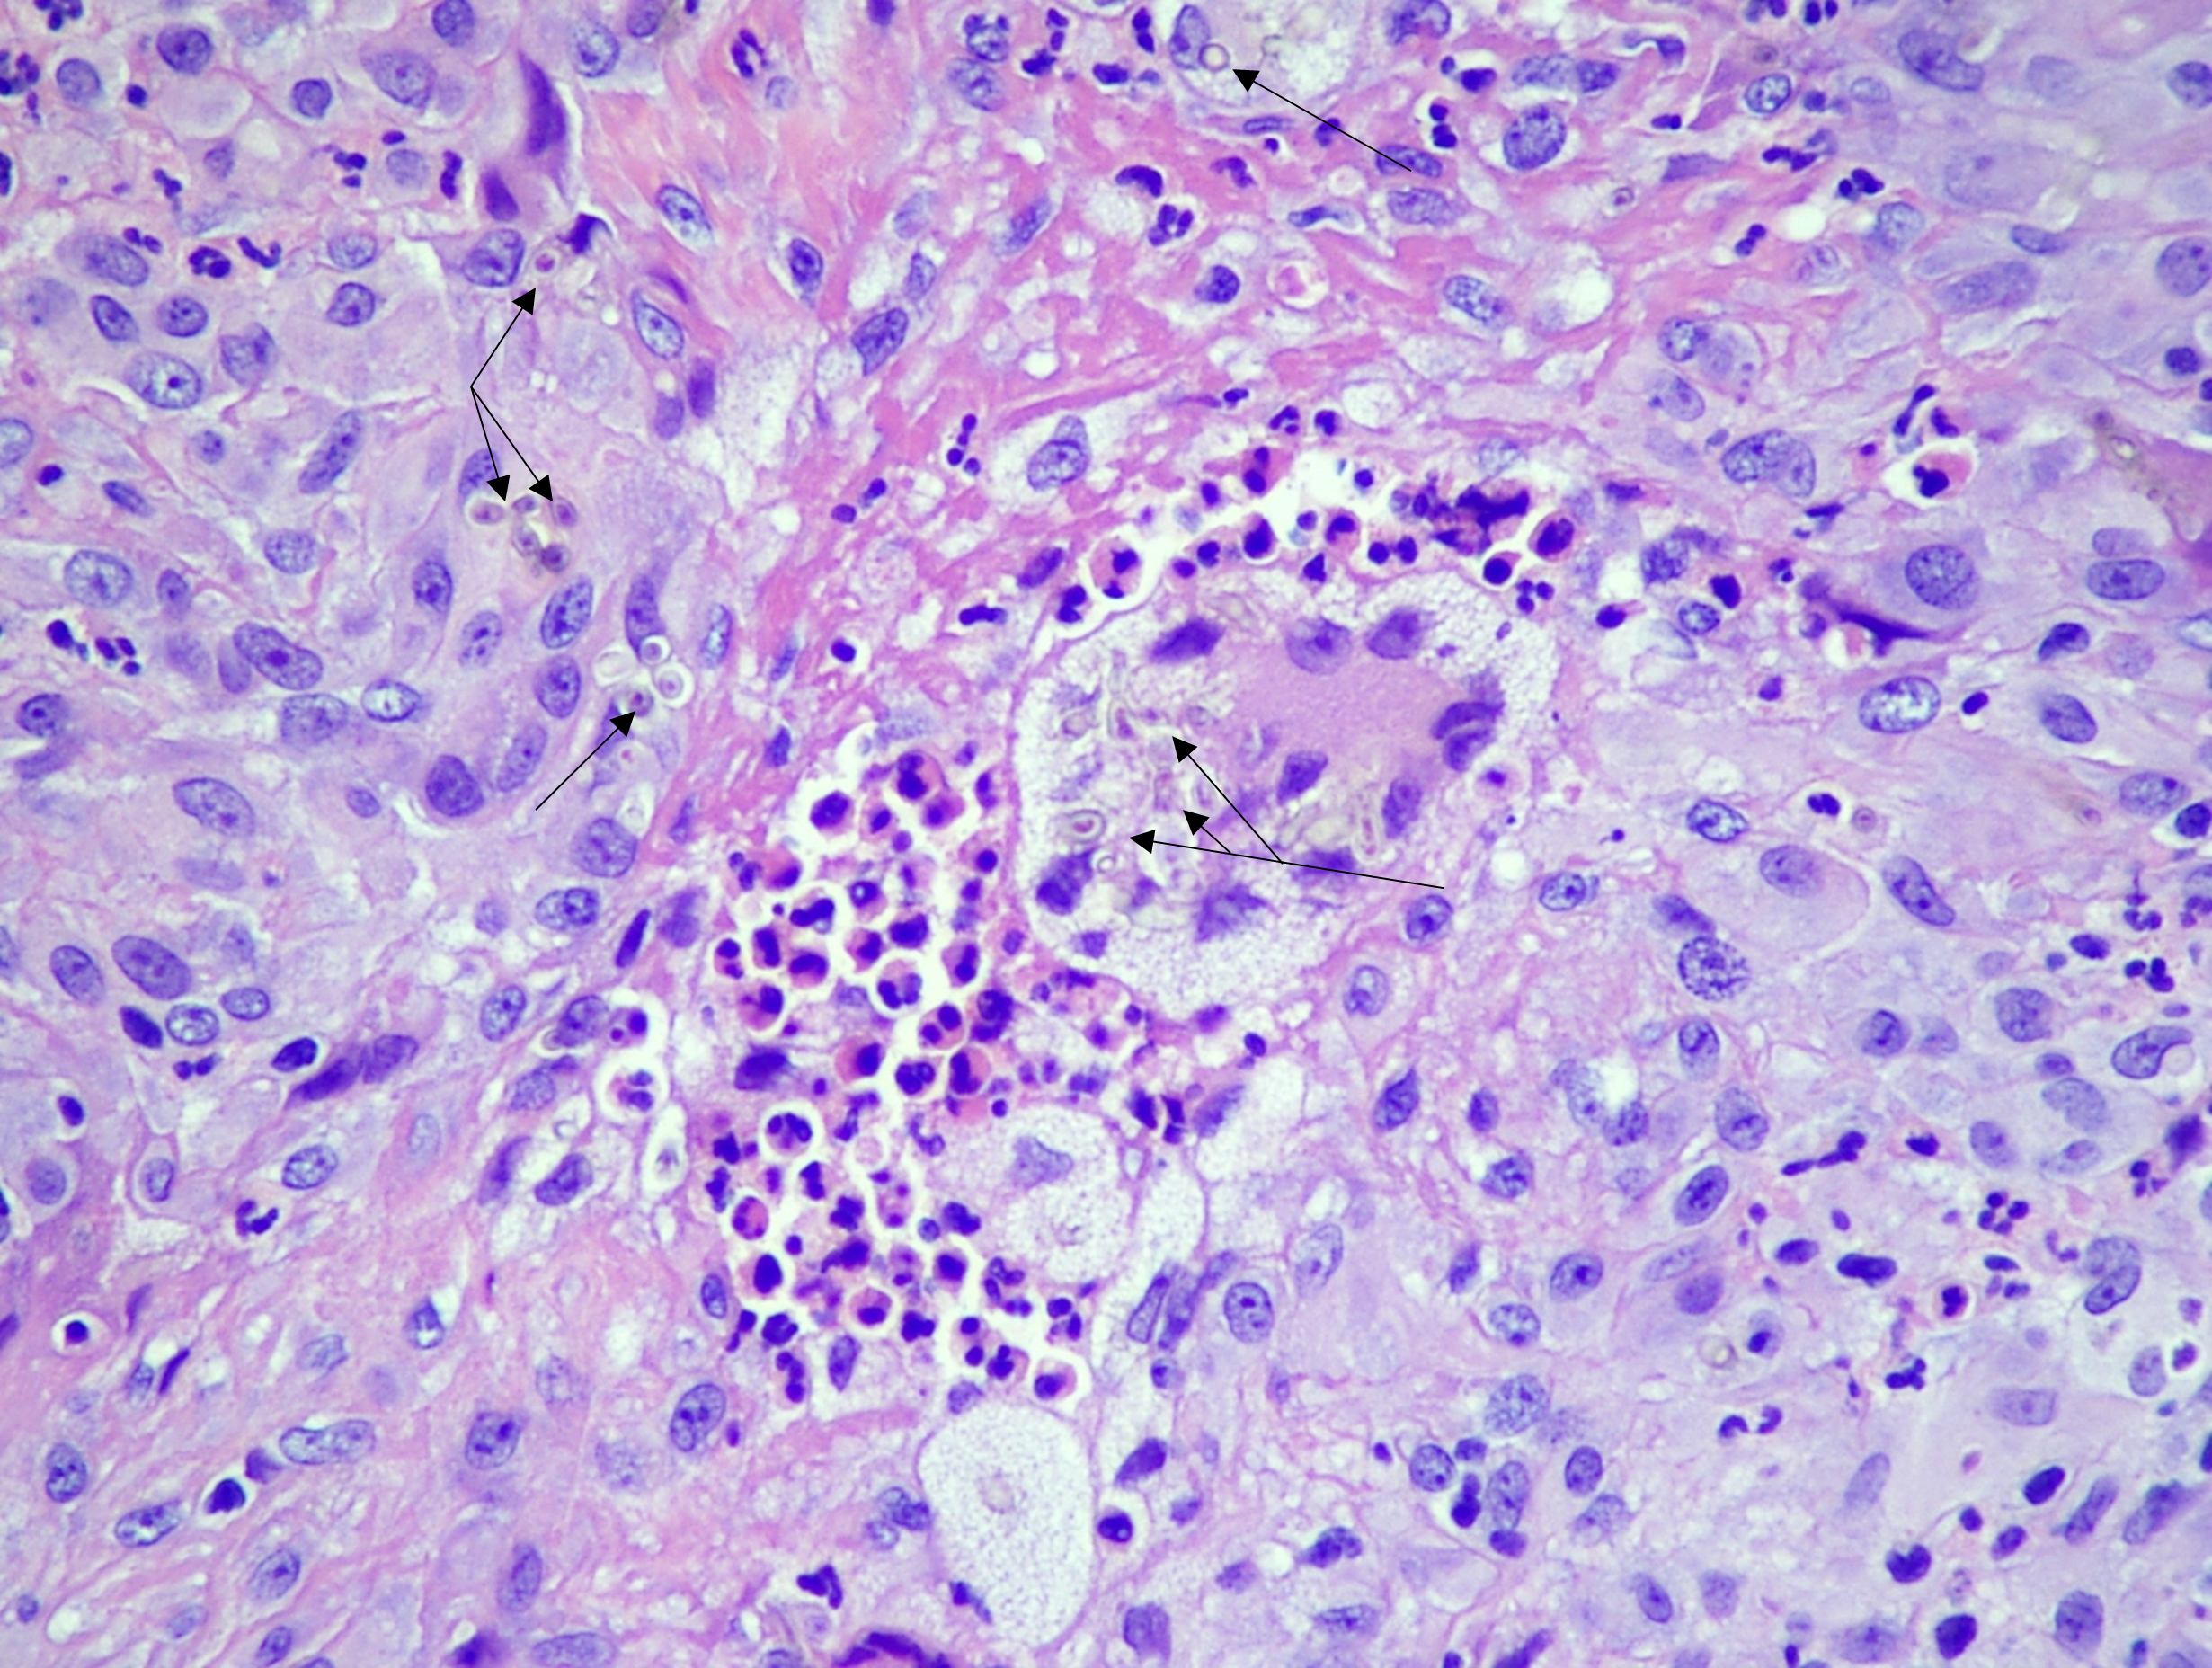

Following excisional biopsy, histopathology revealed a relatively circumscribed lesion with suppurative granulomatous dermatitis and numerous pigmented hyphae observed on hematoxylin and eosin stained slides (H&E; [Figures 2-3]). A diagnosis of phaeohyphomycosis was made; the patient’s methotrexate was held and an infectious disease (ID) consult was placed. Precautionary blood cultures were drawn which remained negative following five days of incubation. The patient was started on a course of empiric oral doxycycline for two weeks which he completed. At presentation for ID follow up, the patient felt well and denied constitutional symptoms or recurrence of the thumb lesion. Physical exam revealed no associated sporotrichoid lesions (lymphocutaneous spread of infection) or palpable lymphadenopathy. ID recommended a 3-month course of oral itraconazole as secondary prophylaxis, which was completed without adverse effects or recurrence of symptoms.

Laboratory diagnosis of phaeohyphomycosis is reliant on histopathological evaluation, as surgical debridement is often necessary for management. In this setting, darkly pigmented, septate hyphae invading tissue in a nonspecific background of inflammation may be observed.1 H&E staining is generally sufficient to confirm diagnosis; however, special stains that can highlight fungi, namely Grocott-Gomori methenamine silver (GMS) or periodic acid-Schiff (PAS) stains, can outline the presence of hyphal elements. Additionally, melanin production can be highlighted using Fontana-Masson staining. Careful evaluation and interpretation of fungal cultures, when collected, are important as results can be complex given the ubiquitous nature of many etiological agents, particularly from non-sterile anatomical sites. Additionally, there are no alternate methods routinely available to aid in diagnosis, outside of culture, to specifically identify etiologic agents of phaeohyphomycosis.3 Importantly, optimal antifungal therapy for these infections remains unclear due to a lack of randomized control trials and relative infrequency of presentation.